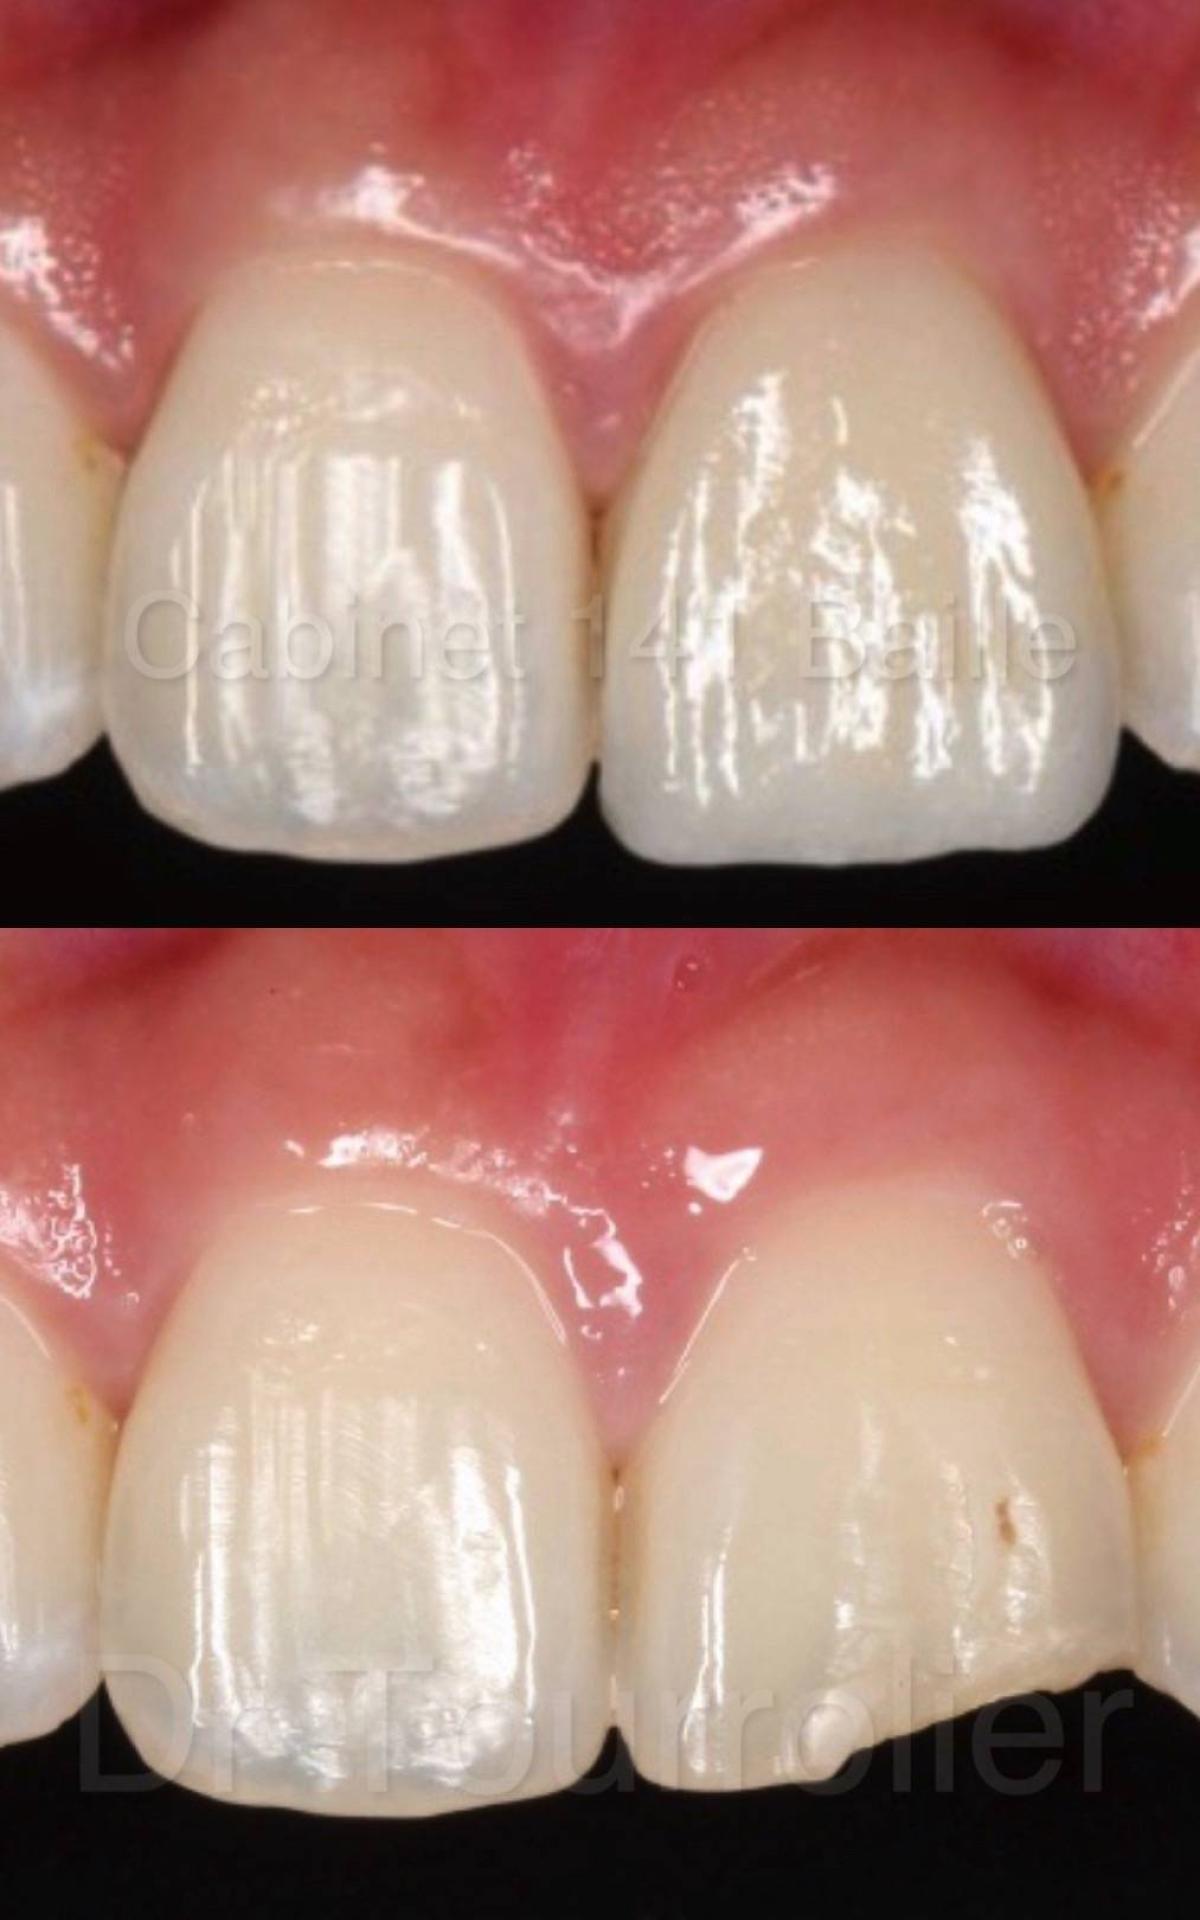

Les facettes dentaires : une évolution importante dans la dentisterie esthétique.

Les facettes dentaires sont de fines pellicules de céramique qui peuvent être stratifiées et qui sont collées en apposition sur les dents pour corriger des anomalies de forme ou de teinte.

Elles permettent une correction esthétique du sourire sans délabrement de la dent.

La référence en matière de résultat esthétique pour les facettes dentaires est de mettre en œuvre comme dans notre cabinet les facettes pelliculaires stratifiées céramiques comme les facettes Emax® que nous utilisons.